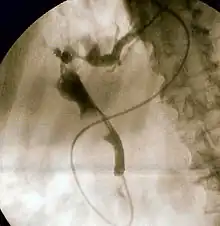

| Duodenoscopy image of pus extruding from the ampulla of Vater, indicative of cholangitis | |

The gold standard test for biliary obstruction is still endoscopic retrograde cholangiopancreatography (ERCP). This involves the use of endoscopy (passing a tube through the mouth into the esophagus, stomach and thence to the duodenum) to pass a small cannula into the bile duct. At that point, radiocontrast is injected to opacify the duct, and X-rays are taken to get a visual impression of the biliary system. On the endoscopic image of the ampulla, one can sometimes see a protuberant ampulla from an impacted gallstone in the common bile duct or the frank extrusion of pus from the common bile duct orifice. On the X-ray images (known as cholangiograms), gallstones are visible as non-opacified areas in the contour of the duct. For diagnostic purposes, ERCP has now generally been replaced by MRCP. ERCP is only used first-line in critically ill patients in whom delay for diagnostic tests is not acceptable; however, if the index of suspicion for cholangitis is high, an ERCP is typically done to achieve drainage of the obstructed common bile duct.[1]